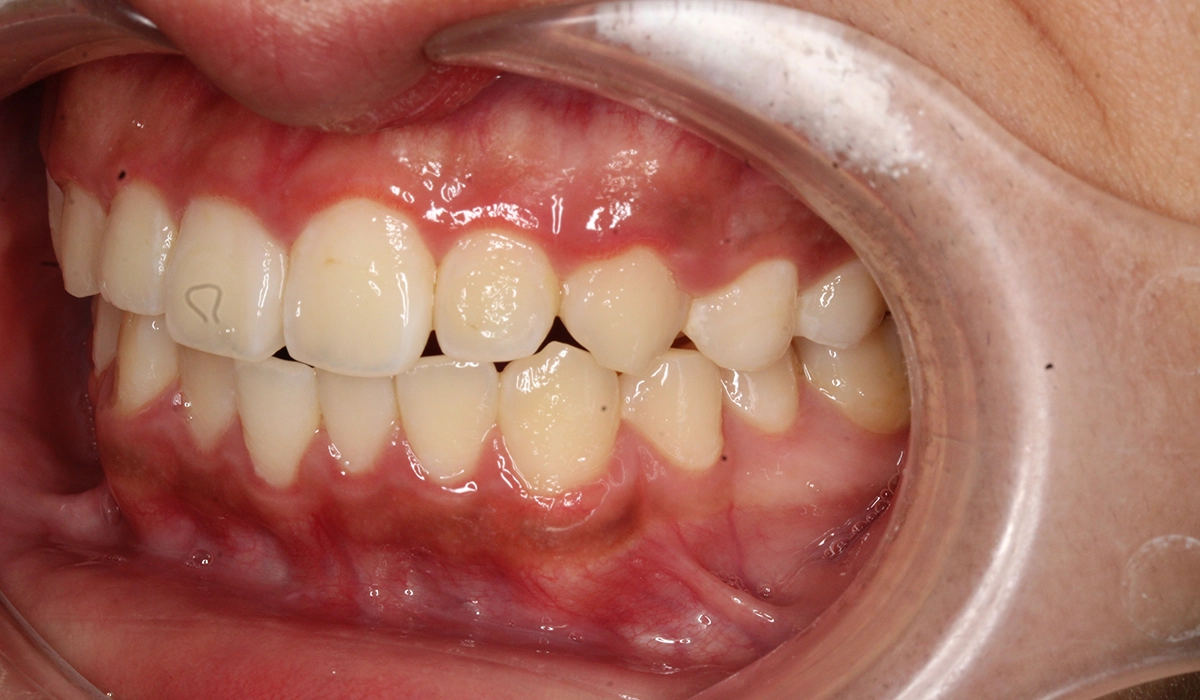

術後:右側